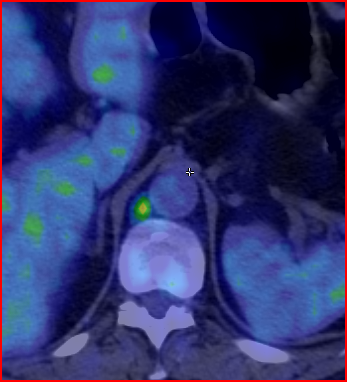

More complex anatomic structures (spine, the base of the skull, facial and hip bones) can be imaged more confidently with SPECT scans. On one hand, they provide a more accurate spatial localization and on the other, with their superior contrast resolution, they are able to differentiate lesions even if planar exams are negative or uncertain. SPECT-CT can characterize the CT morphology of the lesions with pathologic uptake. Thus, it is capable to provide a definitive diagnosis. (Figure 4.)

Image

a

b

c

d

e

4. Bone scintigraphy, prostate cancer. The image set shows the characterization of multiplex increased activity uptake. Posterior whole body scan (a). SPECT-CT coronal fusion images (b,d), CT examination (c,e). Sclerotic lesions in the pelvic bones are suggestive of osteoplastic metastases (b,c), small joint arthrosis at LIII-IV segments, more expressed on the left side (b,c), spondylosis on the right side at LIV-V segments (d,e). (The increased activity spot on the whole body scan, at the left cubital region, is correspondent to the paravasation of the iv. radiopharmaceutical.)